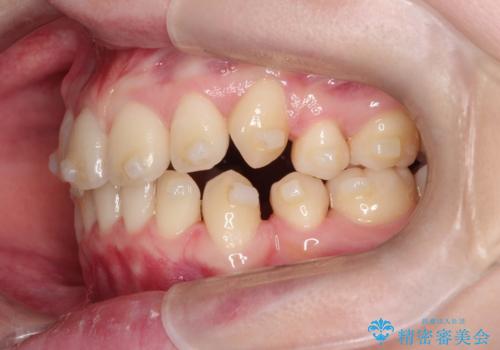

- 八重歯が気になるとのことでご相談いただきました。診察すると、歯列のスペース不足により犬歯が外側に飛び出している状態でした。このままでは歯を並べるスペースが足りないため、抜歯矯正が必要と判断。治療は目立ちにくいインビザラインで行い、歯の移動をサポートするためにゴムかけ(顎間ゴム)を併用する計画を立てました。

抜歯後、インビザラインを用いて少しずつ歯を移動させ、空いたスペースに八重歯を整列させました。さらに、ゴムかけを行うことで上下の噛み合わせを適切に調整。治療後は、八重歯が綺麗に並び、バランスの取れた歯並びと自然な噛み合わせを実現できました。患者様にも「仕上がりがとても綺麗で、口元の印象が変わった」とご満足いただきました。